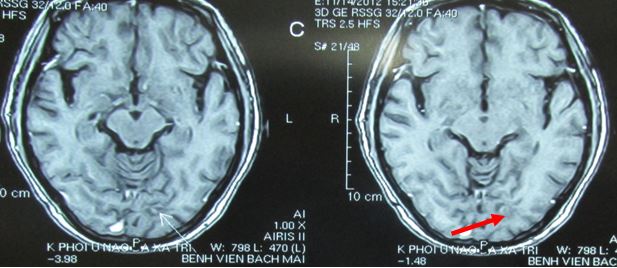

+ Sau điều trị 16 tháng

- Về lâm sàng: bệnh nhân rất tốt, tỉnh táo tiếp xúc tốt, trở lại công việc bình thường, không đau đầu, đau xương, vận động đi lại tốt.

- Về chất chỉ điểm u: các chất chỉ điểm u sau 16 tháng điều trị đều về giá trị bình thường

- So sánh trên hình ảnh CT u phổi di căn não trước và sau điều trị (ĐT)

Hình 9: tổn thương não tiêu biến hoàn toàn, lâm sàng hoàn toàn bình thường